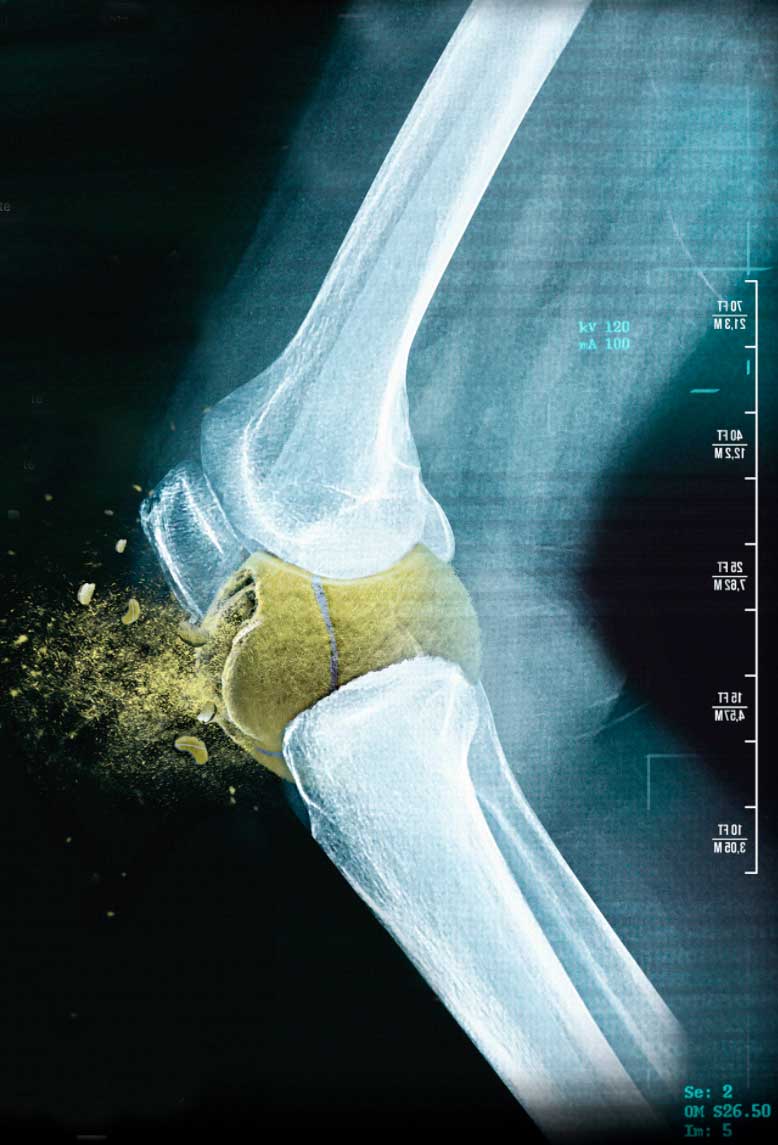

• • Lesiones De Meniscos

Vasculares, nerviosas, articulares y óseas que se traducen en fracturas conocidas como edema óseo.

Pueden afectar las articulación del cuello, hombros, tórax, pelvis, caderas, muslos, rodillas, piernas, tobillos o el pie, es decir, cualquier estructura del cuerpo está expuesta o tiene el riesgo de sufrir una lesión.